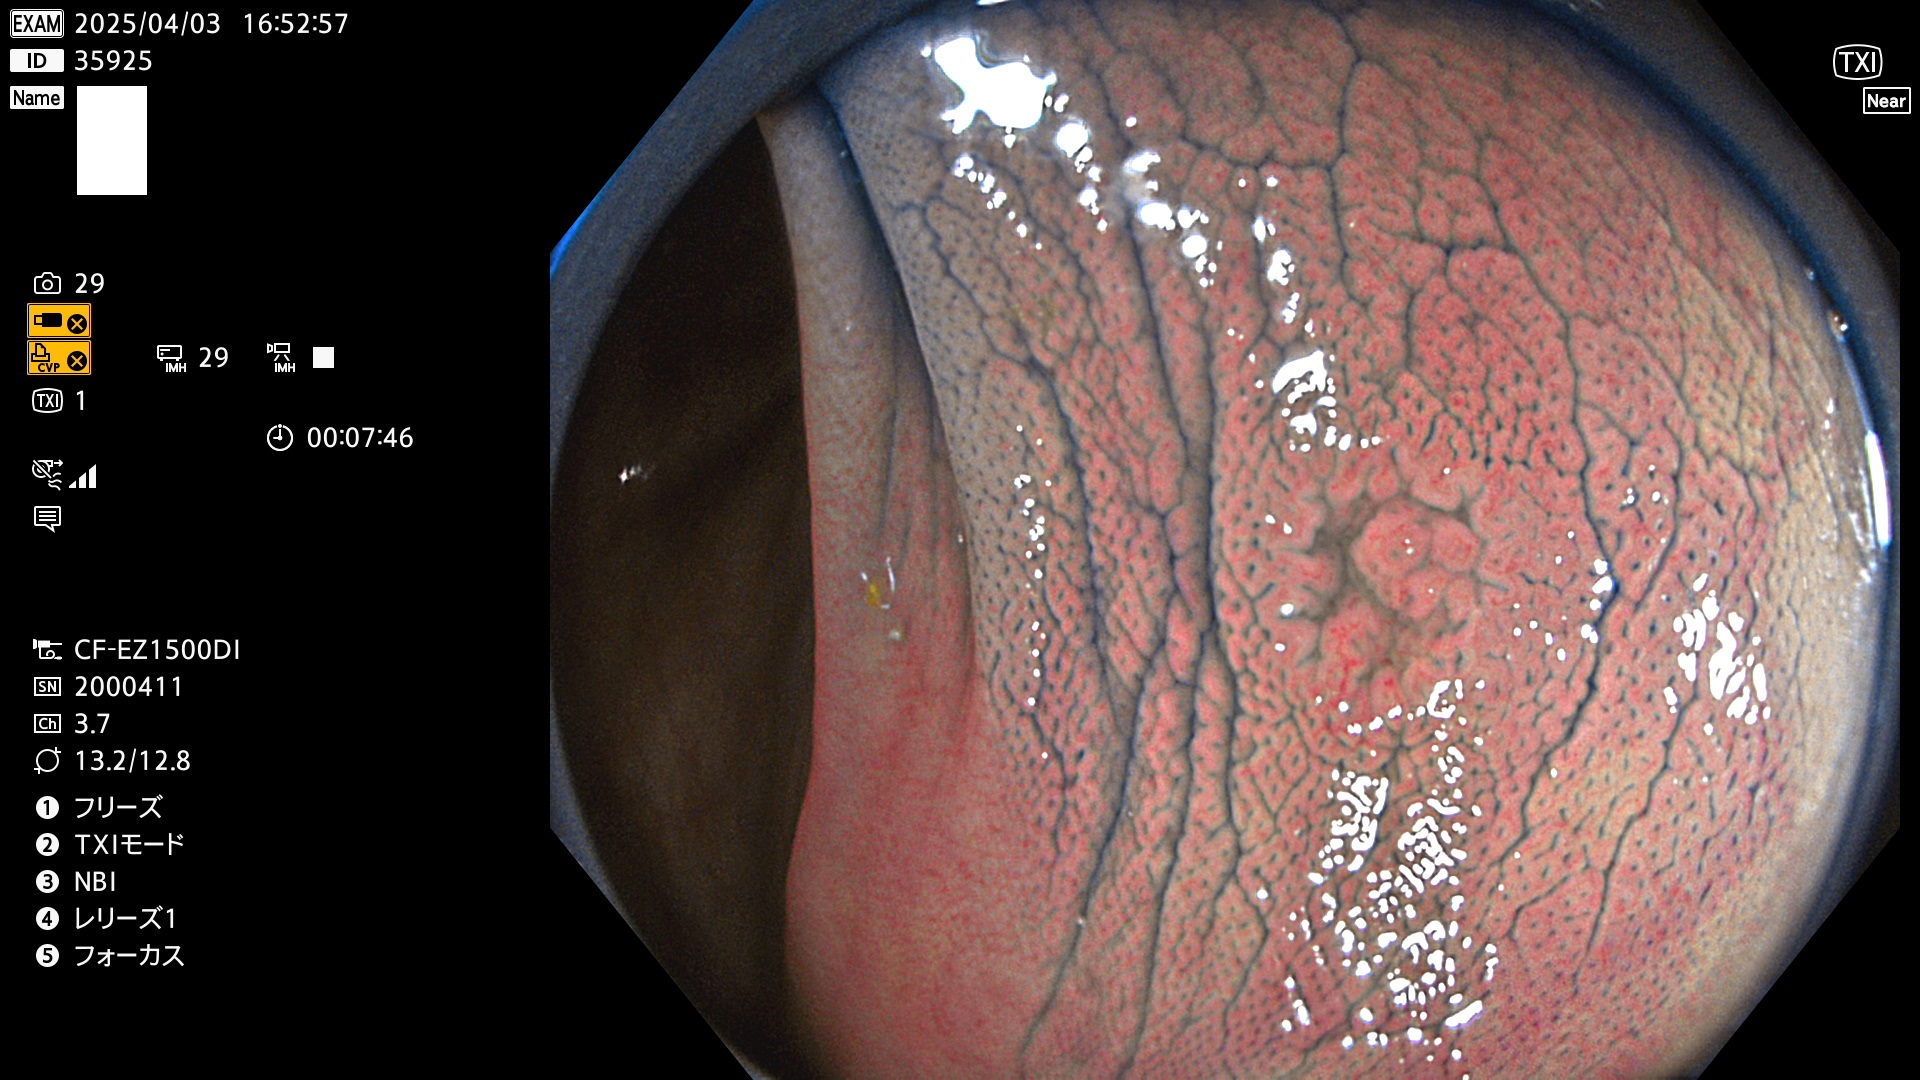

今週のUb、Uc型腺腫

完全に平坦な物をUb、陥凹している物をUcと呼びます。Ubは認識が困難で、Ucはびらん(炎症)と紛らわしいために見落とされやすく、「内視鏡後・大腸癌」の原因になります。

抽出の対象期間 2025年4月3日〜4月6日の4日間(48件の検査)4個 (4/48=8%)